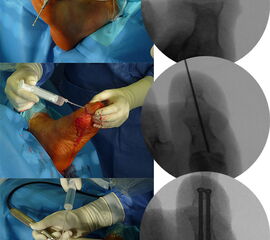

Zur Korrektur der Fehlstellung und zur Ulkus-Behandlung kann in minimalinvasiver Technik über ein mediales Portal eine Walzenfräse in das Interphalangealgelenk eingebracht werden. Über ein zweites laterales Portal wird nach Resektion der Gelenkflächen der Knochenabrieb ausgespült. Sobald ausreichend Knochen reseziert ist, kann die Zehe gestreckt werden. Die beiden abgetragenen Knochenflächen werden im Sinne einer IP-Arthrodese aufeinandergestellt. Es erfolgt dann die Transfixation der Arthrodese mittels ein bis zwei, über die Spitze der Endphalanx eingebrachten Zugschrauben. Problematisch ist es, wenn sich an dieser Stelle unverändert ein Ulkus befindet. In diesem Falle ist die Transfixation der Arthrodese mit zwei perkutan eingebrachten, schräg verlaufenden Kirschner-Drähten weniger risikoreich. Der Eintrittspunkt der K-Drähte befindet sich hier medial und lateral im Bereich der Endphalanx. Bei persistierender Fehlstellung kann je nach Vorspannung eine Tenotomie der EHL- und/oder der FHL-Sehne durchgeführt werden. Normalerweise entspannt sich die Sehne durch die Knochenresektion und den damit verbundenen Längenverlust ausreichend. Zur Korrektur der Fehlstellung „wird die Knochenlänge an die Sehnenlänge angepasst“.

Um die Steilstellung des ersten Os metatarsale und die damit verbundene Entwicklung eines plantaren Ulkus unter MTK-1 zu verhindern, kann in minimalinvasiver Technik durch eine schräg verlaufende, dorsalbasige Keilosteotomie im proximalen Anteil des Os metatarsale I das Metatarsaleköpfchen angehoben werden. Diese Maßnahme führt zu einer Druckreduktion und in der Regel zu einer Abheilung des Ulkus. Die Osteotomie wurde 1998 erstmalig in der offenen Technik beschrieben, wird aber inzwischen auch in minimalinvasiver Technik durchgeführt 25. Über einen dorsomedialen Hautschnitt wird am ersten Strahl ein dorsalbasiger, nach distal geöffneter Keil reseziert (Abb. 11). Der Eintrittspunkt der Fräse befindet sich knapp distal des Tarsometatarsale-I-Gelenks. Die plantare Kortikalis des Os metatarsale I wird dabei erhalten. Die Breite des dorsalen Keils bestimmt das Ausmaß der Korrektur und kann durch Verwendung einer entsprechenden Fräse modifiziert werden. Durch einen Keil mit einer Basis von 3,4 mm lässt sich das Os metatarsale I um ca. 5° anheben. Hat der dorsale Keil eine Basis von 6,7 mm, wird die Achse des Os metatarsale I um 10° nach dorsal korrigiert (Abb. 12). Wird eine Korrektur von ca. 5° angestrebt, bietet sich an, eine Fräse mit einem Durchmesser von 2 mm zu verwenden. Der Substanzverlust bei einem Schnitt liegt bei 2-2,5 mm. Für eine weitere Knochenresektion wird die Osteotomie durch plantaren Druck auf das Os metatarsale I Köpfchen geschlossen und die Fräse nochmals durch die geschlossene Osteotomie geführt. Durch mehrmalige Wiederholung dieser Prozedur lässt sich die Korrektur sehr genau einstellen. Für eine Korrektur von 10° oder mehr kann eine Keilfräse mit entsprechend größerem Durchmesser verwendet werden. Nach Schließen der Osteotomie erfolgt die temporäre Fixation mittels eines K-Drahtes und die Osteosynthese mit einer oder zwei Zugschrauben. Die Nachbehandlung beinhaltet eine sechswöchige Ruhigstellung im Verbandsschuh unter Fersenbelastung.